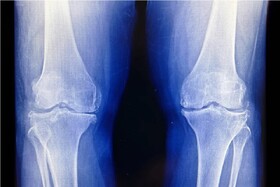

آرتروز زانو

آرتروز، بیماری شایع تخریبکننده مفاصل است که موجب درد، سفتی و تورم شده و دامنه حرکتی فرد را کاهش میدهد. این بیماری اغلب موجب مشکلاتی در زانوها، لگن و دستها میشود، هر چند میتواند در سایر مفاصل بدن نیز مشاهده شود.

متخصص ارتوپدی با تأکید بر اینکه آرتروز زانو در اغلب موارد با معاینه بالینی و رادیوگرافی ساده قابل تشخیص است، گفت: انجام تصویربرداریهای غیرضروری نهتنها کمکی به درمان بیمار نمیکند، بلکه موجب تحمیل هزینههای اضافی به بیمار و سیستم سلامت میشود.